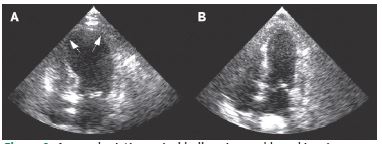

During the preoperative evaluation, the ECG and 2D echocardiogram were normal (Figure 1). However, the patient’s condition later deteriorated with an increased dose of noradrenaline and vasopressor support, and a Point-of-Care Ultrasound (POCUS) examination revealed hypokinesia in both the apical and mid-regions of the heart, along with apical ballooning, indicating left ventricular dysfunction (Figure 2). A cardiologist subsequently confirmed these findings. The blood gas analysis showed metabolic acidosis with a lactate 3 mmol/lt. Further investigations are shown in Table 1.

Figure 2: Arrow depicting apical ballooning and hypokinesia.

Arterial blood gas analysis revealed metabolic acidosis with elevated lactate levels. A bedside POCUS (Point-of-Care UltraSound) was performed, which showed apical ballooning and apical hypokinesia, indicating left ventricular dysfunction with an ejection fraction of 40%, later confirmed by the cardiologist (Figure 5).

Figure 5: Apical ballooning with hypokinesia in apical 4-chamber view.